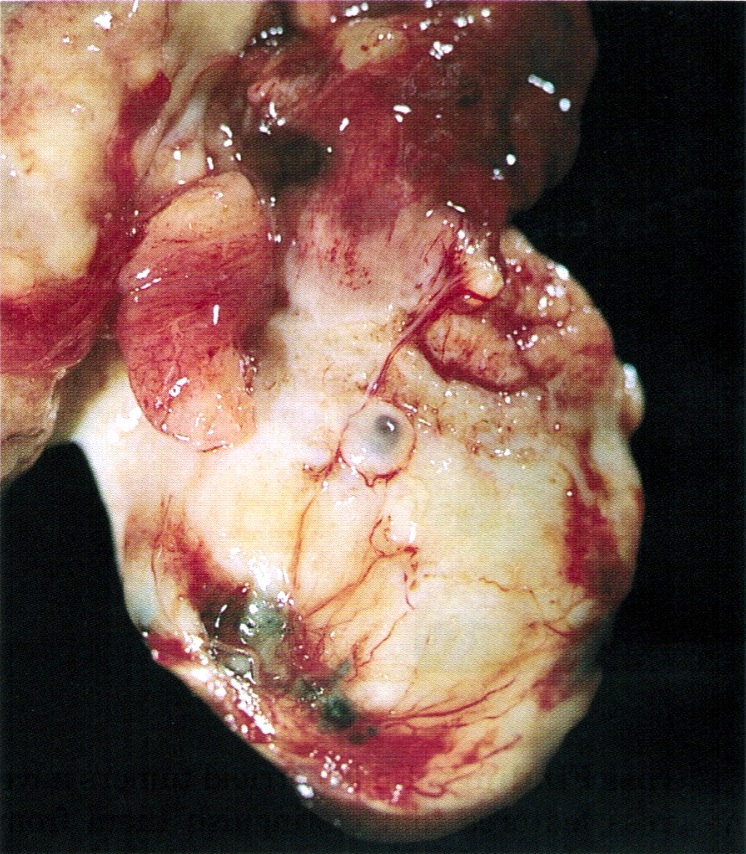

Gross description

- Cystadenoma: usually unilocular cyst

- Adenofibroma: firm, white nodule with honeycomb appearance to cut surface, sometimes in the wall of an endometriotic cyst (J Obstet Gynaecol 2011;31:352)